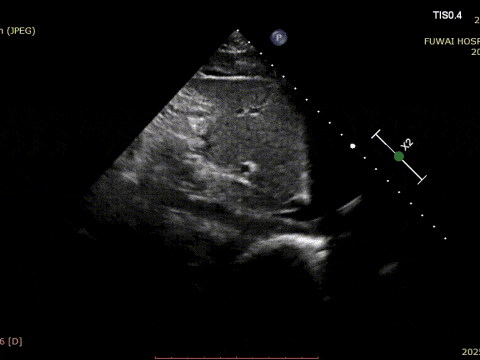

At Fuwai Hospital Shenzhen, Dr. Lu Yaoxing's team recently performed a successful transcatheter closure of a secundum atrial septal defect (ASD) using a MemoSorb biodegradable occluder in a 34-year-old male patient with a rare coronary anomaly.

1 El TEA fue central en la ubicación, con un diámetro medido de aproximadamente 8,1mm (vista bicaval) y 8,2mm (vista aórtica de eje corto).

El procedimiento fue guiado por TTE siguiendo el procedimiento PAN desarrollado en el Hospital Fuwai. Esta técnica de imagen en tiempo real sin radiación ofrece una visualización anatómica de alta resolución, lo que garantiza una colocación precisa del dispositivo y minimiza las complicaciones, especialmente en pacientes jóvenes en edad reproductiva.